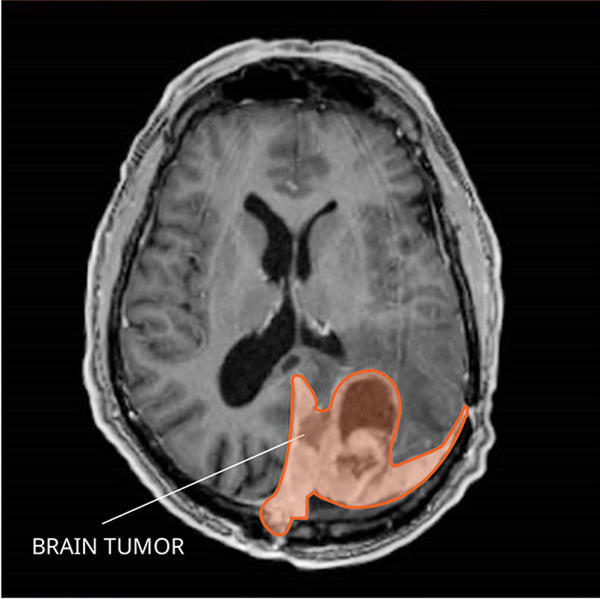

Magnetic resonance imaging (MRI) with or without gadolinium

MRI uses a magnet, radio waves, and a computer to make a series of detailed pictures of areas inside the brain. A substance called gadolinium is injected into a vein. The gadolinium collects around the cancer cells so they show up brighter in the picture. This procedure is also called nuclear magnetic resonance imaging (NMRI).